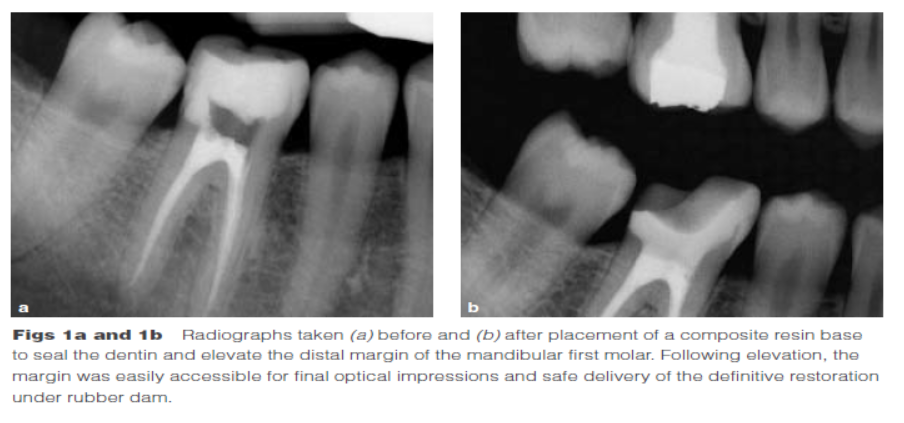

Dietschi和Spreafico在1998年提出了另一種方法,即在間接修復(fù)體的下面放置一個復(fù)合樹脂基底來取代冠向提升邊緣(圖1)。這個方法即我們所知的齦壁提升術(shù)(DMG)是在橡皮障隔離下完成的?(This procedure,…,is performed under rubber dam isolation following the placement of a matrix.)如今,DME(齦壁提升術(shù))通常與IDS(即刻牙本質(zhì)封閉術(shù))聯(lián)合使用來促進間接粘接修復(fù)體的粘接和齦邊緣的封閉。此外,邊緣的齦上提升,粘接復(fù)合樹脂基底被用于封閉牙本質(zhì)、加強潛在牙尖?(reinforce undermined cusps),充填倒凹(fill undercuts),以及為嵌體/高嵌體修復(fù)提供必要的幾何形態(tài)。

DME是用一個改良彎曲的成型片接堆放復(fù)合樹脂來提升齦壁高度,使其能夠在修復(fù)過程中使用橡皮障封閉邊緣,可以在固化前適當(dāng)?shù)囊瞥嘤嗟膹?fù)合樹脂。DME應(yīng)該在即刻牙本質(zhì)封閉(IDS)之后,在使用橡皮障的條件下,且僅在邊緣可被改良的成型片適當(dāng)隔離時直接獲得。否則,這個技術(shù)不能使用。在最終取印前,需要拍攝咬合翼片來評估復(fù)合樹脂在齦邊緣區(qū)域的密合度(有無懸突或缺陷)。同樣需要仔細隨訪來評估軟組織的健康和是否需要外科手術(shù)干預(yù)。只要可能,在牙髓治療前就應(yīng)通過DME術(shù)制造假壁,使根管治療更完善(圖2、3)。圖4展示了一個典型DME術(shù)的適應(yīng)癥。